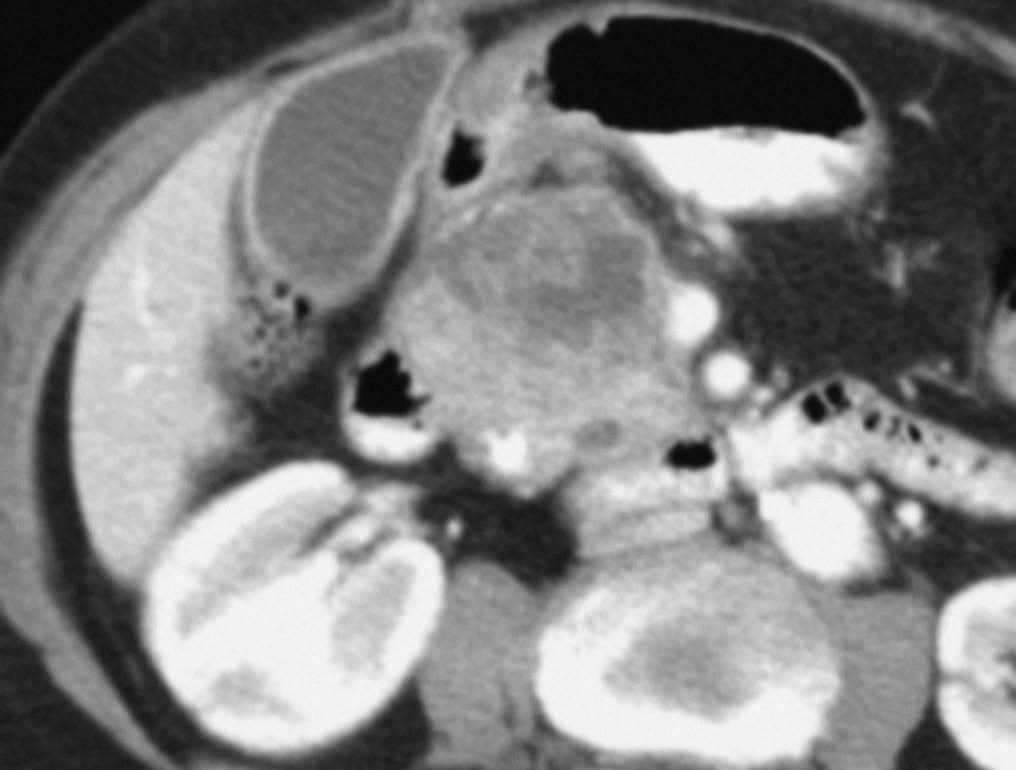

Fig. 3.--Estudio de tomografía computarizada con contraste endovenoso en fase venosa portal en un paciente con neoplasia de páncreas. Masa heterogénea mal definida en el cuerpo pancreático. (A) Sección axial que no permite identificar el eje esplénico-mesentérico-portal. (B) La reconstrucción multiplanar oblicua coronal, orientada en el plano del confluente venoso demuestra de forma clara la disminución del calibre de la vena porta en su origen y de la vena mesentérica superior en su confluencia con la vena porta (puntas de flecha), que permite establecer el diagnóstico de infiltración venosa local, mostrando la longitud del segmento venoso afectado.